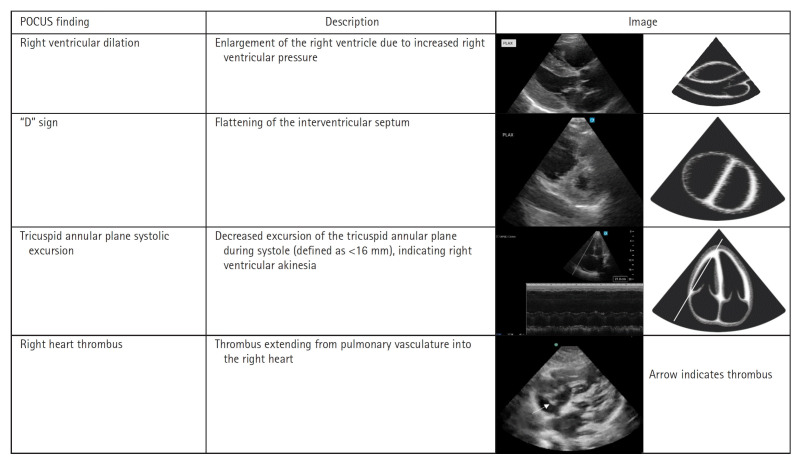

Extracorporeal membrane oxygenation (ECMO) has been increasingly employed in the emergency department for patients with a potentially reversible cause of cardiac arrest. We present the case of a young female patient with an in-hospital cardiac arrest who was found to have severe right heart strain on point-of-care ultrasound (POCUS), suggesting a massive pulmonary embolism. Rapid bedside diagnosis using ultrasound expedited bedside cannulation and initiation of ECMO as a bridge to surgical thrombectomy, and ultimately the patient survived with full neurologic function. With its ready availability and increasing acceptance by consultants, POCUS should be incorporated into cardiac arrest algorithms as the standard of care to rule in thrombotic and obstructive causes of cardiac arrest.

Abstract Image